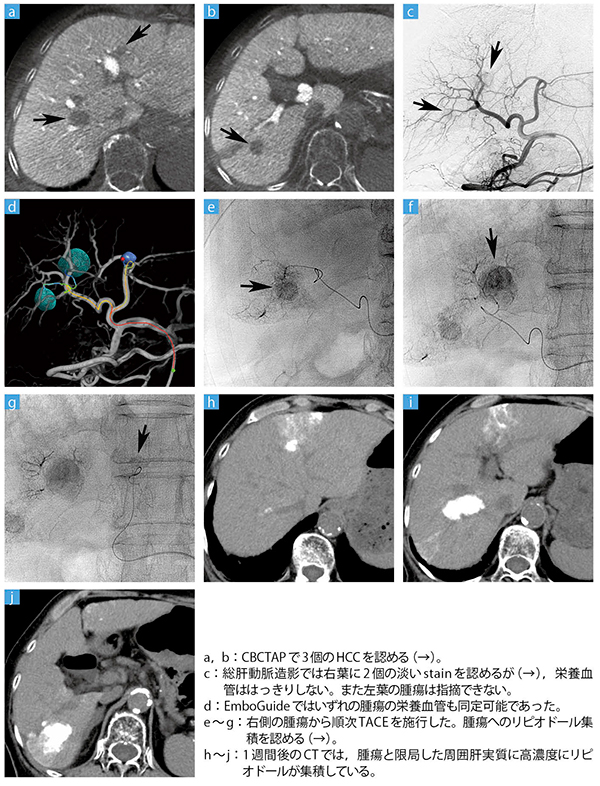

症例:XperCTとEmboGuideを用いたTACE

実際のTACE手技では,まずAllura Xper FD20のXperCTで経動脈性門脈造影下CBCT(CBCTAP)を行う。さらに上腸間膜・腹腔動脈を撮影し,カテーテルを肝動脈に挿入して総肝動脈,あるいは左右肝動脈造影を行った後にCBCTHAを実施する。

CBCTHAでは,2相の撮影を行う。このDual phase XperCTはフィリップス社独自の技術で,最短4秒間隔で2回のスキャンが可能である。2相撮影では,肝細胞がん(HCC)に特徴的なコロナ濃染が描出可能であり,この所見はAPシャントなどの多血性偽病変との鑑別に役立つ。また,治療効果を確実にするために,TACEではその濃染域を含めて塞栓することが重要となる。実際の手技では,370mgI/mL造影剤を注入し1相を撮影した30秒後に,2相を撮影する。

治療対象となる腫瘍が決まったら,操作室の診療放射線技師がEmboGuideを操作し,栄養血管の解析を行う。CBCTHAの1相上で作成したターゲットと3D血管像を重ね合わせた画像上で解析開始点を決め,自動解析ボタンをクリックすると,数秒後に腫瘍の栄養血管がカラー表示される。仮想ターゲットは10個まで設定でき,栄養血管は同時に解析されるが,表示する腫瘍の個数や順序は任意に変更でき,手技の進行状況に応じた表示が可能である。また,CBCTHAで腫瘍の描出がされない場合は,CBCTAPの画像を参照する。宮山部長は,「私たちは,腫瘍の濃染域だけをターゲットにすれば治療がうまくいくとは考えていません。腫瘍周辺の治療安全域も含めて塞栓することが大事です。そのためにも,EmboGuideでは,マージンを含めてターゲットを作成するようにしています。腫瘍サイズが25mm未満であれば最低5mm,25mm以上であれば10mmをマージンにしています。この安全域の選択が,栄養血管の同定がうまくできるかどうかのキーポイントになります」と説明する。EmboGuideで栄養血管を同定した後,それらを順次選択して塞栓し,すべての栄養血管が塞栓された時点で終了となる。